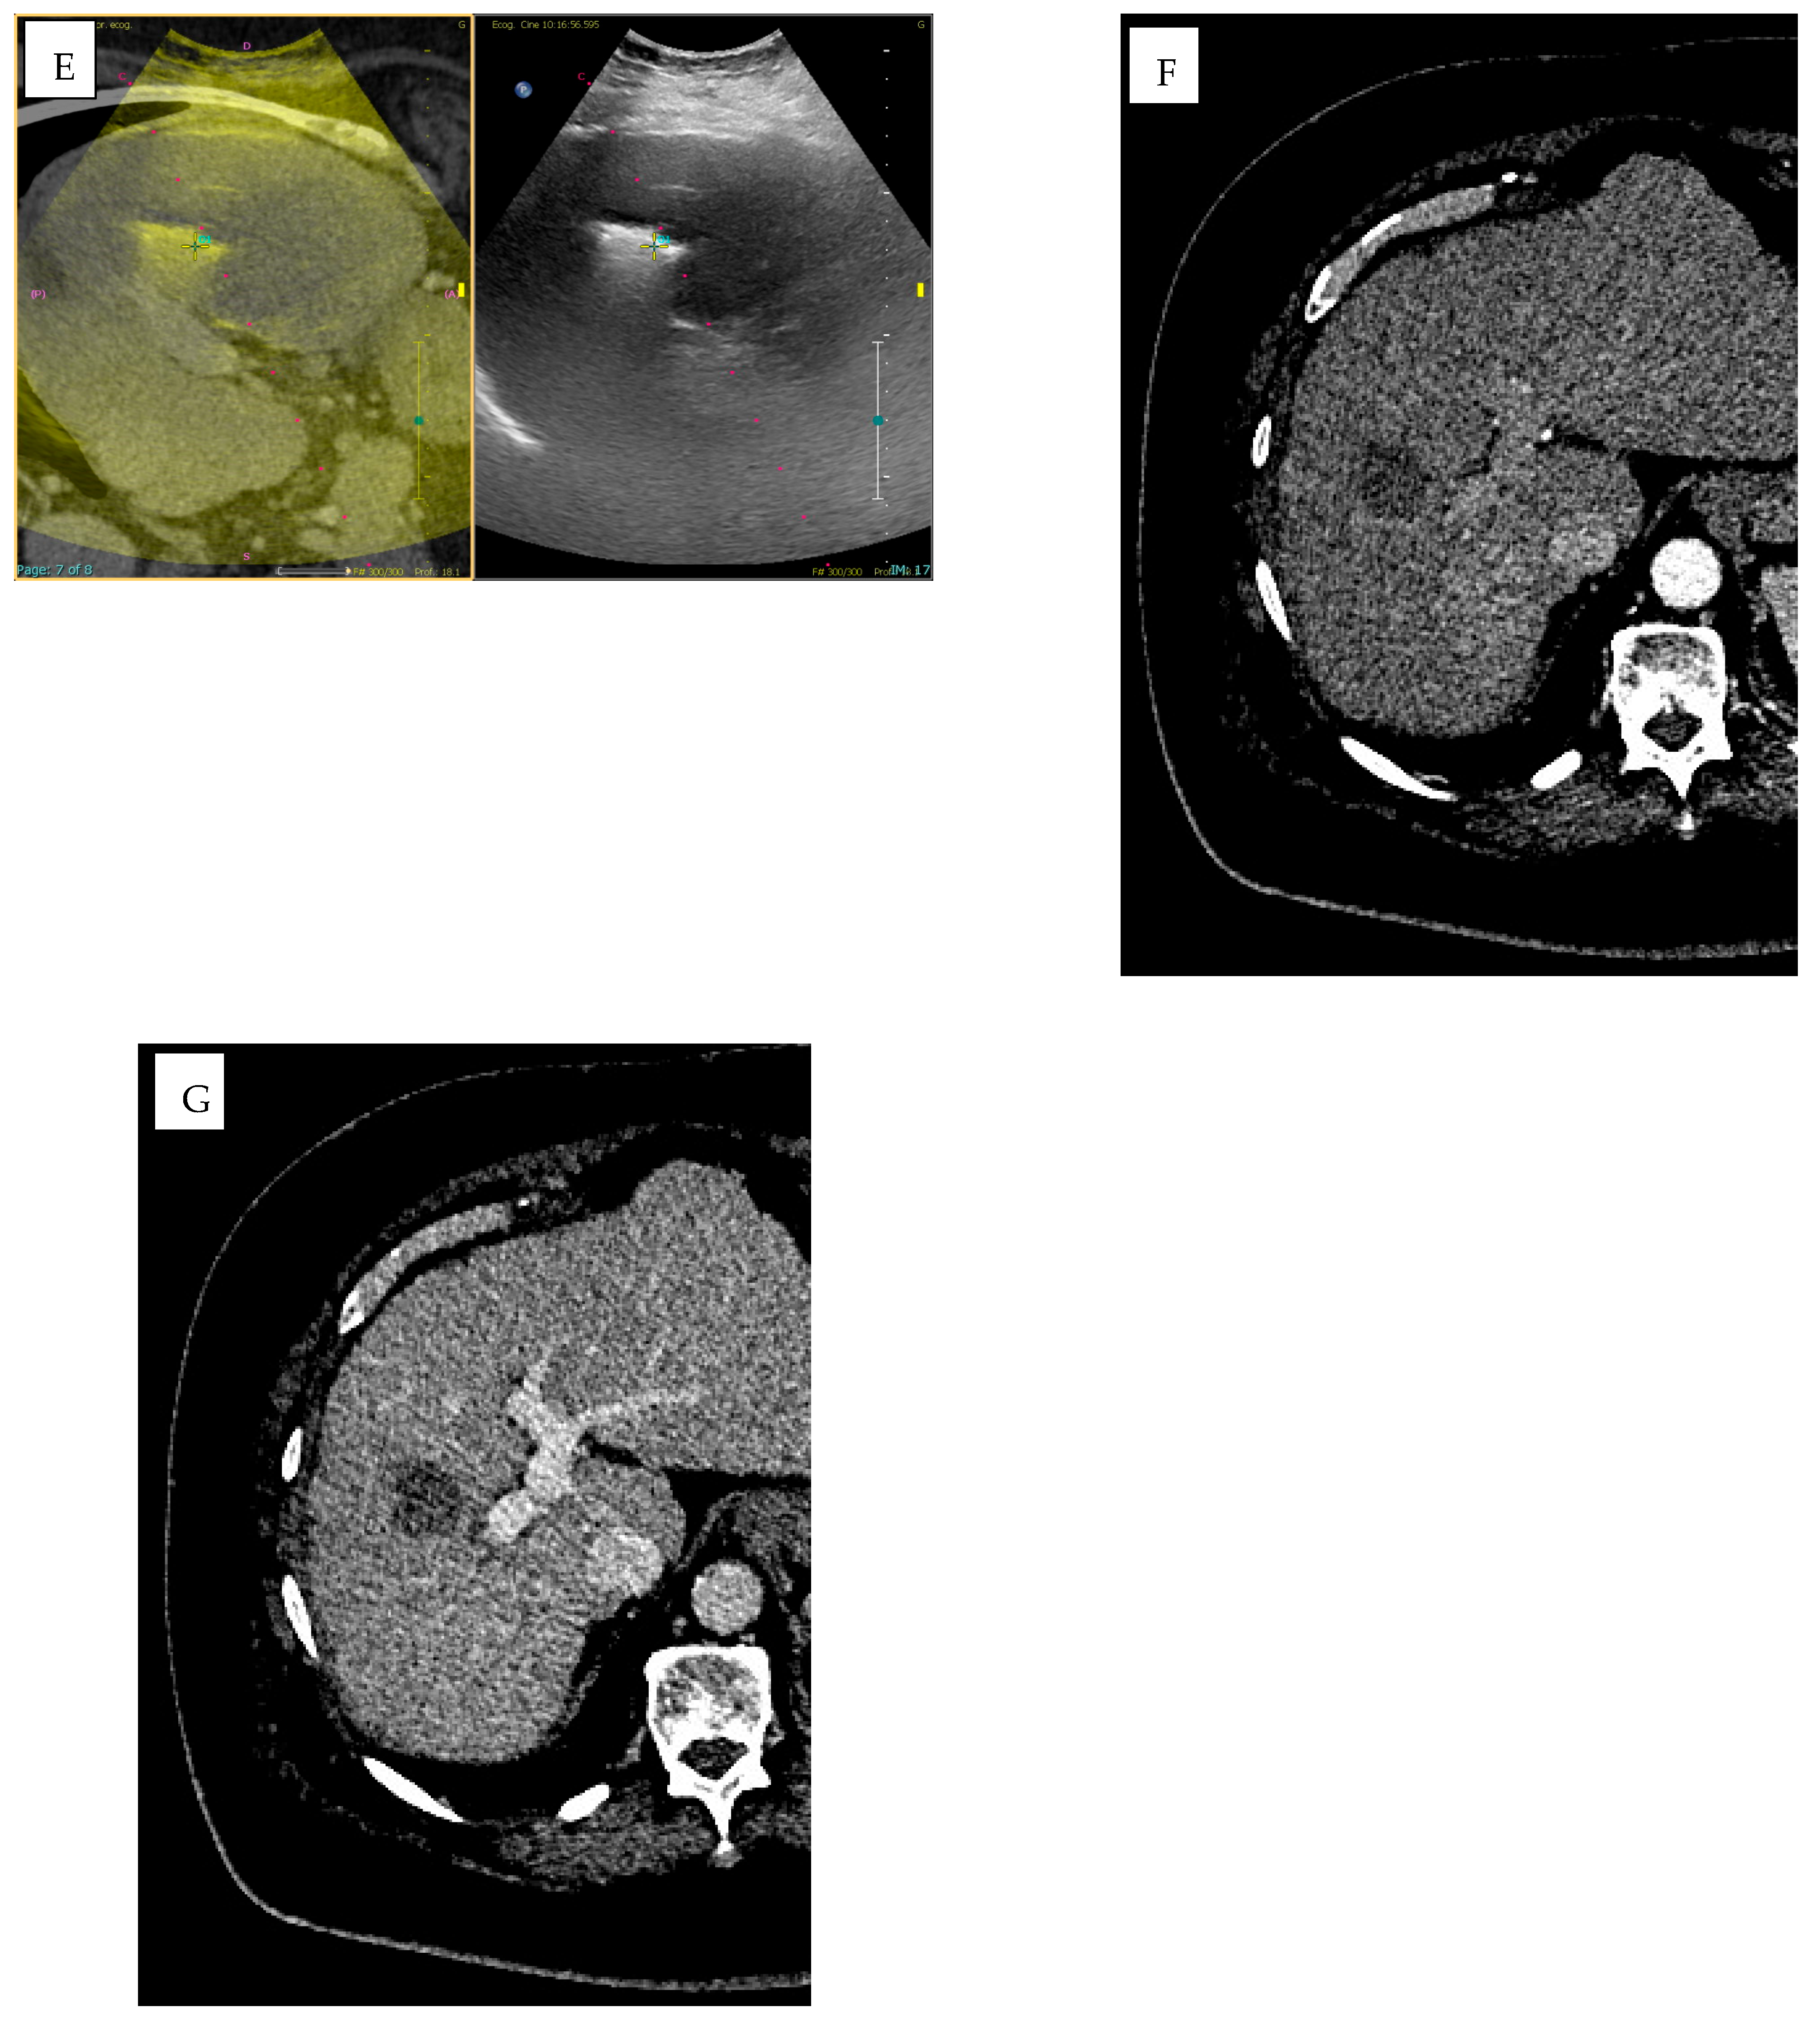

| CBCT and AFD | Imaging guidance/feeder detection | Abi-Jaoudeh et al. [97] | AFD (feeder detection) and vessel segmentation | CBCT, CT, US, Fluoroscopy | Embolization (TACE/TAE), vascular malformation | Improves targeting and procedural accuracy. |

| Imaging guidance/feeder detection | Tacher et al. [98] | AFD (feeder detection) and vessel segmentation | CBCT, CT, US, Fluoroscopy | Embolization (TACE/TAE), vascular malformation | Improves targeting and procedural accuracy. | |

- Chiaradia, M.; Izamis, M.L.; Radaelli, A.; Prevoo, W.; Maleux, G.; Schlachter, T.; Mayer, J.; Luciani, A.; Kobeiter, H.; Tacher, V. Sensitivity and Reproducibility of Automated Feeding Artery Detection Software during Transarterial Chemoembolization of Hepatocellular Carcinoma. J. Vasc. Interv. Radiol. 2018, 29, 425–431. [Google Scholar] [CrossRef]

- Abdelsalam, H.; Emara, D.M.; Hassouna, E.M. The efficacy of TACE; how can automated feeder software help? Egypt. J. Radiol. Nucl. Med. 2022, 53, 43. [Google Scholar] [CrossRef]